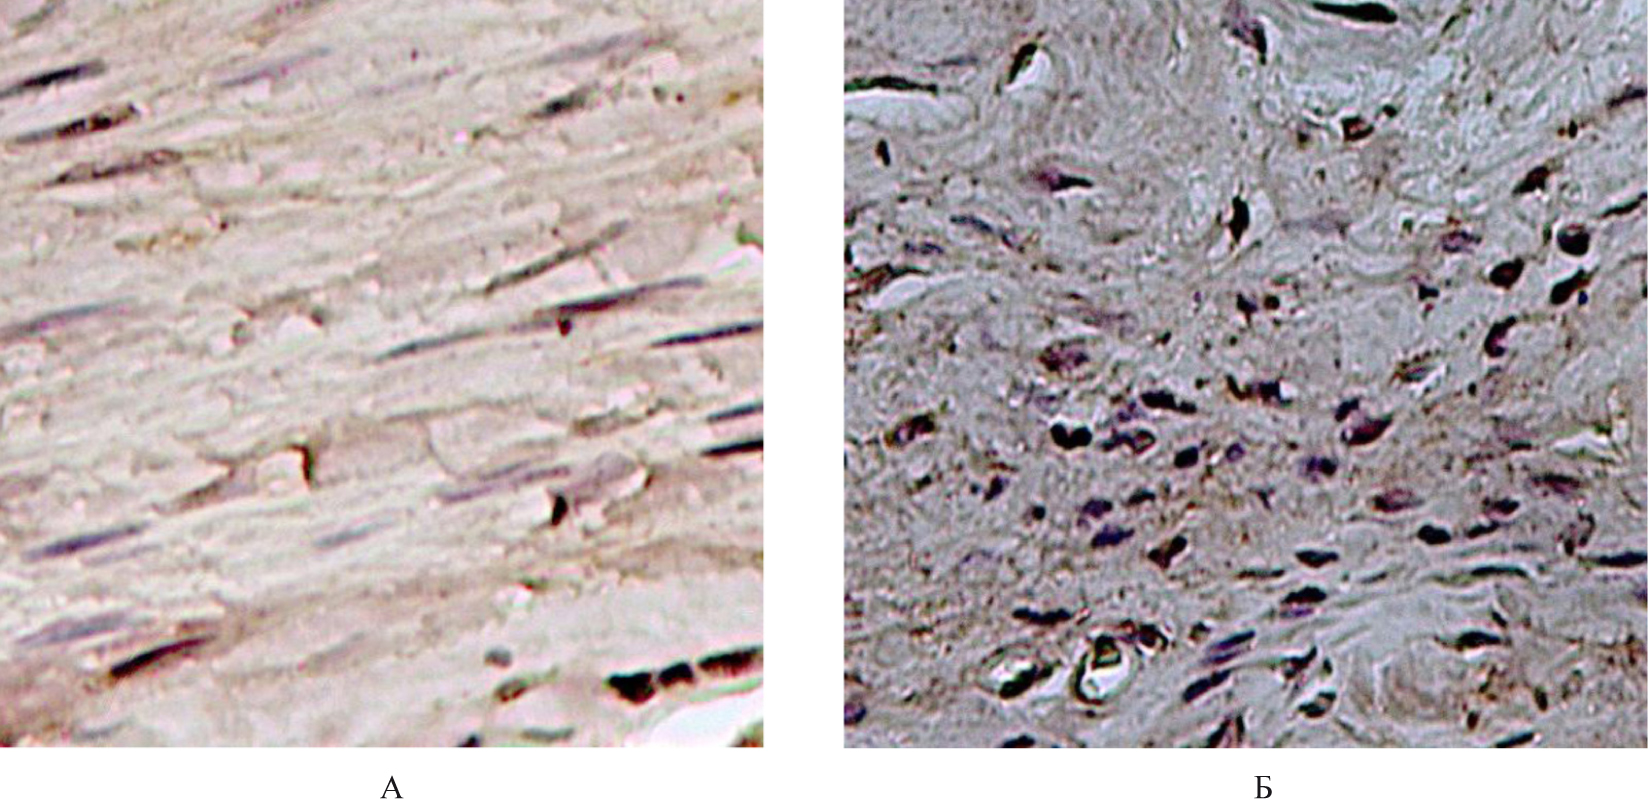

В микропрепаратах сухожилий лабораторных животных из Г1 с использованием антител против ММП1, ММП9, ММП19, ТИМП1 в цитоплазме фибробластов и фиброцитов отмечалась слабо выраженная экспрессия иммунореактивного материала (ИРМ) (1 балл). Клетки воспалительного инфильтрата отсутствовали. Данные результаты соответствовали картине нормального состояния сухожильной ткани (рис. 2).

Рис. 2. Гистологическое строение сухожилия крысы из группы: А – иммуногистохимическое исследование антитела против MMP1, докраска гематоксилином Карацци (ув. × 400), Б – иммуногистохимическое исследование антитела против MMP9, докраска гематоксилином (ув. × 400)